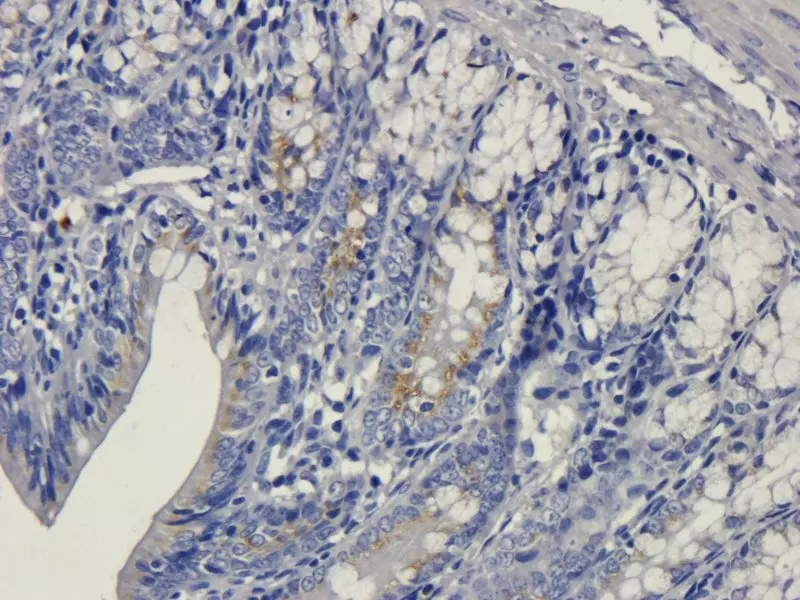

Immunohistochemistry (IHC) is an invaluable tool for researchers in clinical settings and laboratories. A combination of IHC techniques results in clear imaging of specific tissue components. Labeled antibodies are used to bind to specific target antigens in situ and combined with optimized staining, cells and components are visualised with clarity. IHC can provide accurate data revealing distribution, quantity and intensity of expression to enhance and validate your research. Your protocol design will affect your results, the choices within the protocol will impact the quality of the results you achieve. Use Biorbyt’s experience, along with our vast range of high quality products, to support your research at every stage.

IHC is used by researchers globally to diagnose disease, in drug development and in a wide range of biological research. Identification of cells, components, their origins and pathology can be visualised in glorious colour using IHC in isolation or combined with other techniques. Cellular activity in response to specific chemicals can be observed and quantified to understand efficacy during drug development. Modern IHC techniques allow high-throughput, multiparametric, accurate data analysis at all levels of research.

Use a chromogenic substrate or fluorescent dye to detect signal viewed using light or fluorescence microscopy.